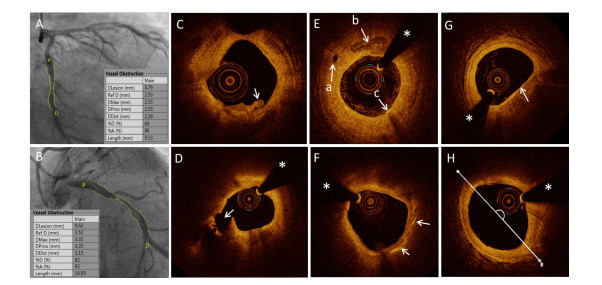

Figure 1. Typical images of patients

(A) A typical CAG image of a patient with STEMI and PE; (B) A typical image of a patient with STEMI and PR; (C) A typical OCT image of a patient with STEMI and PE characterized by intact and rough intima attached by small white thrombus. (D) A typical OCT image of a patient with STEMI and PR characterized by ruptured intima (arrow) backed with a big cavity (pound sign). (E) Representative OCT images, including micro-channel (left arrow), macrophage accumulation (arrow below), and spotty calcification (arrow above); (F) Representative OCT images of cholesterol crystal; (G) Representative OCT images of TCFA; (H) Lipid core determined based on the lipid arc. The asterisk marks the position of the OCT guide wire. CAG, coronary angiography; STEMI, ST-segment elevated myocardial infarction; PE, plaque erosion; OCT, optical coherence tomography; PR, plaque rupture; TCFA, thin-cap fibroatheroma;